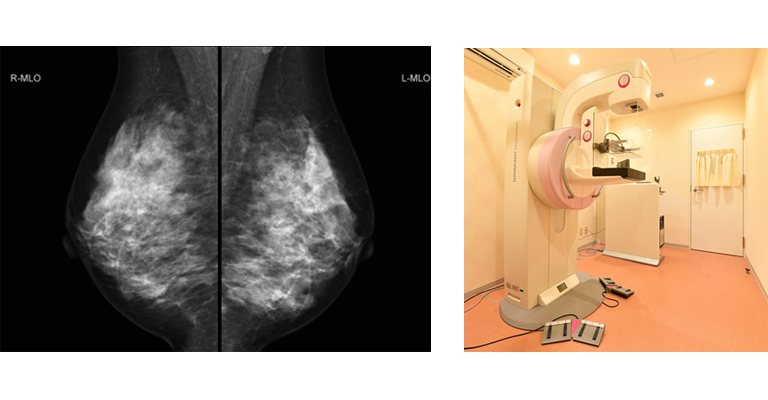

マンモグラフィ+乳腺超音波検査 9,900円(税込)

月曜日~金曜日 PM ※AMご希望の方はご相談ください。

乳がんの早期発見/早期治療に有効なシンプルな検査です。定期的にご受診されている方にもおすすめです。 ★マンモグラフィー検査・乳腺超音波検査は女性の技師が実施致します★